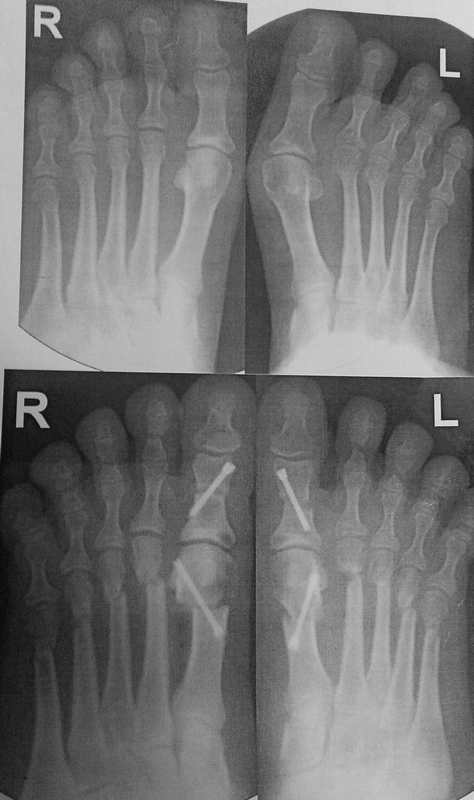

Уважаемые коллеги, я понимаю, что уже утомил вас оперированными стопами, но помогите еще с одним случаем Женщина около 50, активная, оперирована 1 год назад. Тип остеотомии в выписке не указан (похоже с 1-го по 5-ую + фаланги). Сожалею. что фото стопы не удалось выложить, клинически - выраженная девиация всех пальцев стопы слева. Что предпринять? Латеральный релиз, утягивание (лучшего синонима не нашел) медиальной капсулы+остеотомии 4-5 с нормальной повязкой? 1-ый луч - SERI (для жесткости остальных- к нему притянуть), но, головка и так скомпроментирована (или это не брать в расчет?)+ освежение ложняков+ коррегирующая остеотомия 4-5 Weil с фиксацией винтом (или без фиксации?). С фалангами что делать? Кажется, что ничего?

А чего Вы притесняетесь? Насчет "утомил вас оперированными стопами". Такая же ортопедия, как и вся остальная, обсуждаемая на форуме. Да еще сложный ревизионный случай. Изначально то все здорово было. Так бывает, к сожалению, когда все вроде правильно сделано, а в результате не складывается. Почему-то 2 из 10 плюсневых не срослись. На прошлогодней конференции AOFAS был доклад о неудачах после операций на стопе, в котором авторы выделили группу «нестрастальщиков»: пациентов, которые не срастаются без очевидных причин для этого. Может и здесь подобный случай. Из предложенного Вами плана не ясно, зачем делать SERI? Ее ведь сделали год назад. Только не стандартный вариант с фиксацией спицей, а более сложный, с внутренней фиксацией. Возможно, в этом была причина избыточной латерализации головок: подошвенные пластинки 1 и 2 плюснефаланговых суставов тесно связаны. Слишком радикальное уменьшение первого межплюсневого угла за счет латерального смещения головки первой плюсневой привело к дестабилизации нефиксированных остеотомий 2 и 3 плюсневых. И если сейчас еще больше переместить головку первой плюсневой кнаружи, это только усугубит ситуацию. На схеме я показал, в каком положении окажутся 2 и 3 пальцы в случае репозиции головок их плюсневых: расстояния между 1 и 2 лучами итак практически не остается. Я бы в данном случае подровнял внутренний контур головки 1 плюсневой, удалил винт из основной фаланги, выполнил латеральный релиз 1 плюснефалангового, эйкиноподобную остеотомию основной фаланги 1 пальца; репозицию головок 2-3 плюсневых с фиксацией их головок спицами на 4-6 недель и положив в область ложных суставов костную аутостружку или какой-нибудь искусственный заменитель кости. Если при этом пальцы не станут ровнее – выполнил бы остеотомии основных фаланг соответствующих пальцев. Без вмешательства на 4-5 плюсневых.